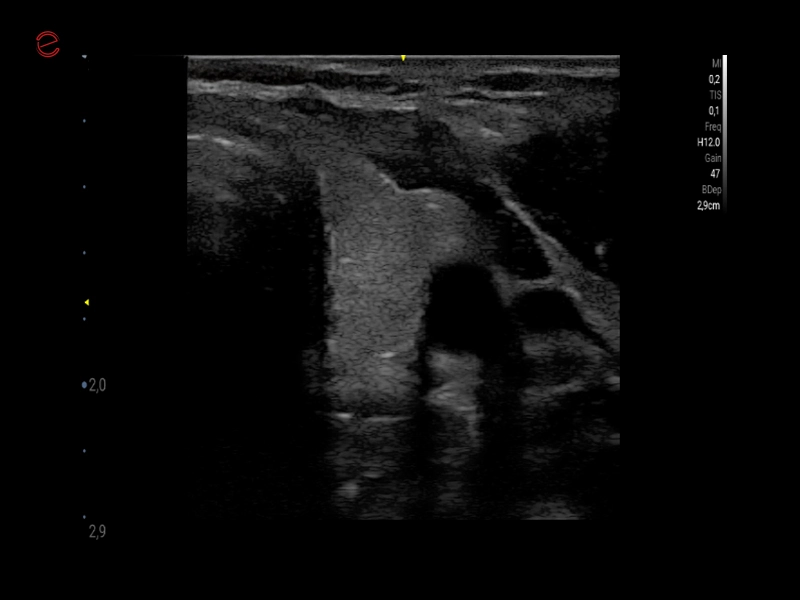

MyLab™9 Platform - Very-superficial linear imaging with Power Doppler algorithm

MyLab™9 Platform - Very-superficial linear imaging with Power Doppler algorithm